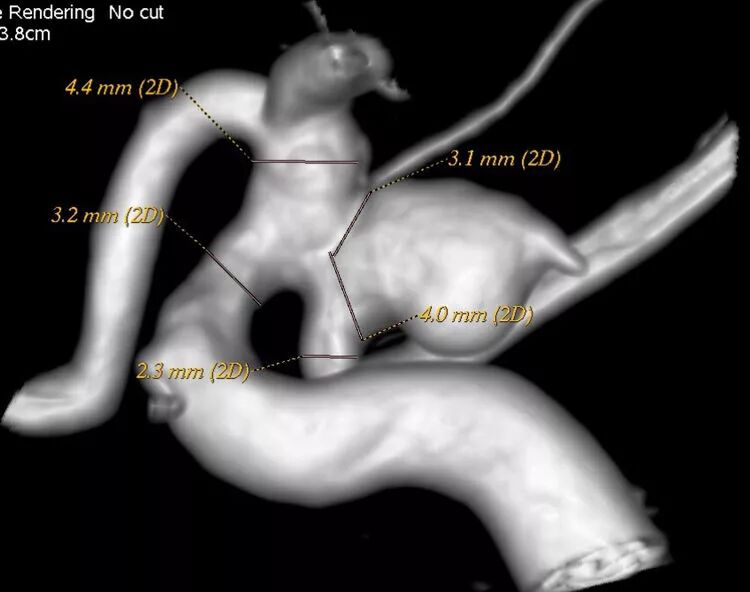

局部观,宽颈,涉及颈内动脉和后交通动脉

椎动脉造影见左侧大脑后动脉P1段很细

栓塞的关键是既要保持颈内动脉通畅,又要保持后交通动脉通畅。双导管单纯填塞;通过颈内动脉释放支架灯笼技术辅助是可选的方案。本例是通过后交通动脉释放支架,利用支架摆尾技术(half-T)来进行栓塞。支架导管塑型

塑型后的形状

Enterprise4.5×22支架半释放,支架尾端的有效段能恰好覆盖全瘤颈

支架有效段完全释放,这个时候开始将支架导管往前顶,让导管头端尽量越过瘤颈远端

支架完全释放

释放后的造影。突入颈内动脉和后交通动脉内的弹簧圈被压入瘤体内

继续填塞,后面就简单了。最后的结果,一共用了四枚弹簧圈,栓塞致密,瘤体及破口都不显影了